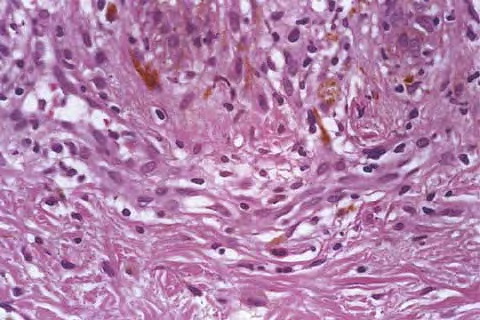

Atlas of skin histopathology

Fixed Drug Eruption =الاندفاع الدوائي الثابت